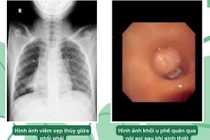

Vừa qua khoa Hô hấp 1 - Bệnh viện Nhi đồng 2 tiếp nhận một bé trai 10 tuổi, ngụ ở An Giang với tình trạng viêm phổi kém đáp ứng điều trị, kéo dài hơn 4 tháng.